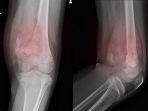

Waspada Kanker Osteosarkoma yang Kerap Menyerang Anak-anak Hingga Orang Dewasa, Berikut Gejalanya

Berikut Gejala Osteosarkoma. kanker ini banyak menyerang anak-anak dan dewasa muda